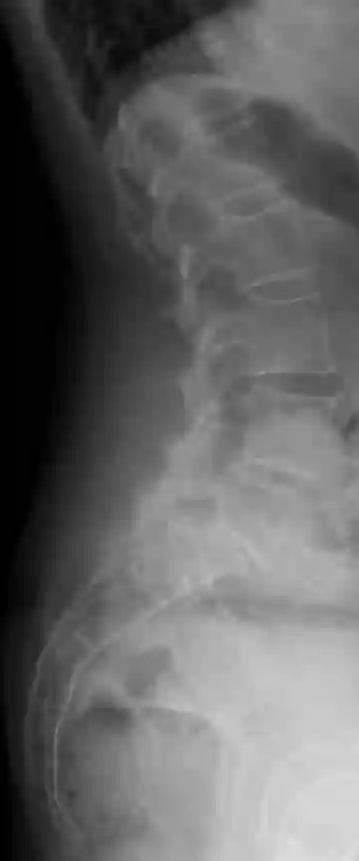

Spondylolisthese LWK5/SWK1

Laterale Röntgenaufnahme eines Patienten mit einer Meyerding Grad 2 Spondylolisthese LWK5/SWK1.